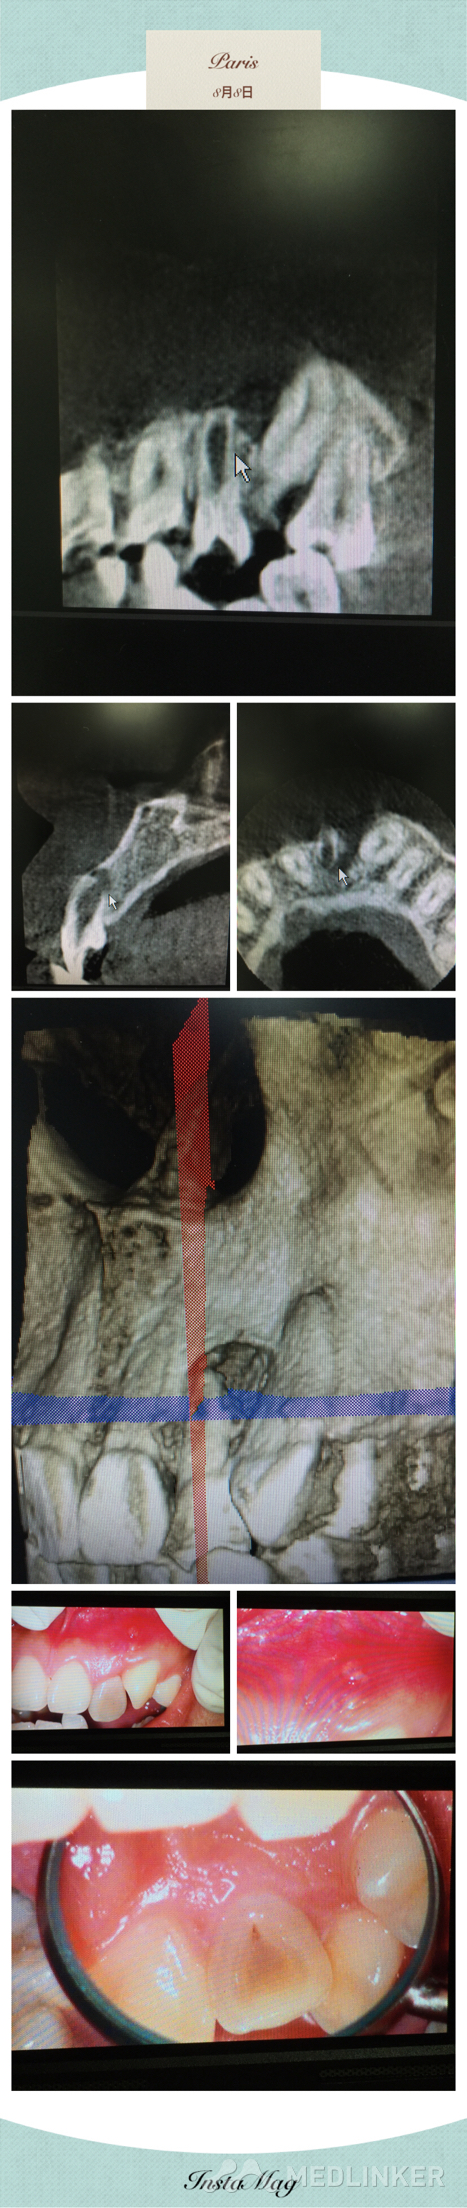

根尖屏障术?

请问在做根尖屏障术时如何将MTA放到根尖处?

根尖孔极为粗大,需要MTA根尖屏障,请问怎么可以充好MTA,根尖没有气泡?